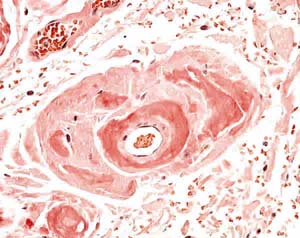

- Proteínas Amiloides: Algunas proteínas tienen una tendencia intrínseca a formar estructuras amiloides, como las fibrillas de amiloide mencionadas anteriormente en el contexto de la amiloidosis. Estas proteínas tienen regiones específicas que favorecen la agregación y el plegamiento inapropiado.

Además, estas proteínas mal plegadas tienden a formar agregados intracelulares o extracelulares. Estos agregados pueden ser tóxicos para la célula y pueden desencadenar respuestas inflamatorias o patologías específicas, como enfermedades neurodegenerativas.